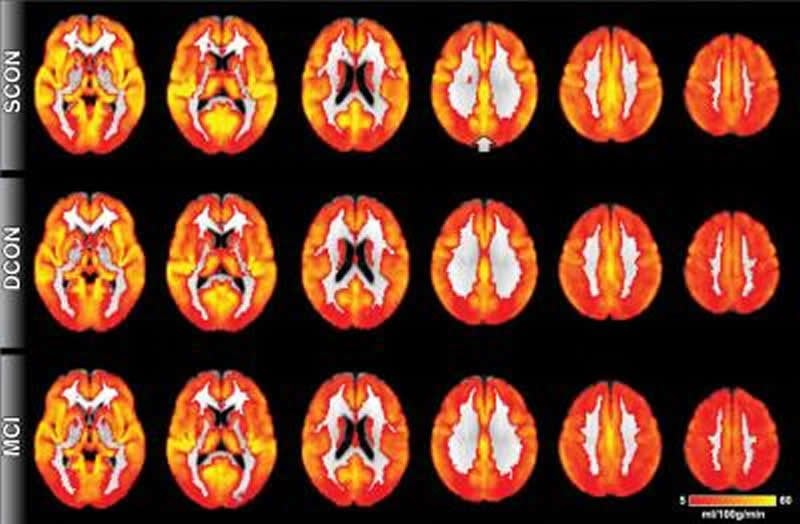

This image shows brain perfusion. Red indicates low perfusion, yellow indicates high perfusion. Overall, the brain perfusion is similar between all three groups. The most prominent difference is present in the posterior cingulate cortex (indicated by the arrow), a region close to the midline in the superior and posterior part of the brain. Control participants who remain stable have higher perfusion as compared to deteriorating controls and MCI. Credit RSNA.

Of the 148 healthy individuals, 75 remained stable, while 73 deteriorated cognitively at 18 months clinical follow-up. Those who deteriorated had shown reduced perfusion at their baseline ASL MRI exams, particularly in the posterior cingulate cortex, an area in the middle of the brain that is associated with the default mode network, the neural network that is active when the brain is not concentrating on a specific task. Declines in this network are seen in MCI patients and are more pronounced in those with Alzheimer’s disease.

The pattern of reduced perfusion in the brains of healthy individuals who went on to develop cognitive deficits was similar to that of patients with MCI.